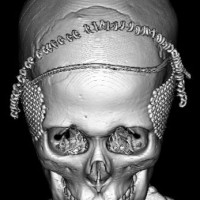

全脳照射後の頭蓋骨の部分的発育不全

2歳くらいで全脳照射を受けた子どもが15歳になりました。前頭骨だけの発育が悪くて額の間がとても狭くて,コメカミの凹みが目立つようになりました。両側の側頭部にチタンプレートを入れて額を広くして頭蓋形成をして,見栄えはとても良くなりました。このような手術を整容的頭蓋形成術といいます。